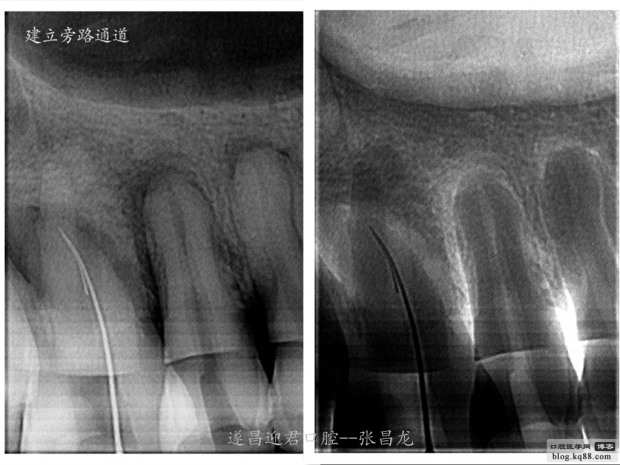

下面是我最近的一個(gè)患者,患者14,15,16均因楔狀缺損導(dǎo)致牙髓壞死,根管治療期間,16的近中頰根發(fā)生了斷針。

建立旁路通道